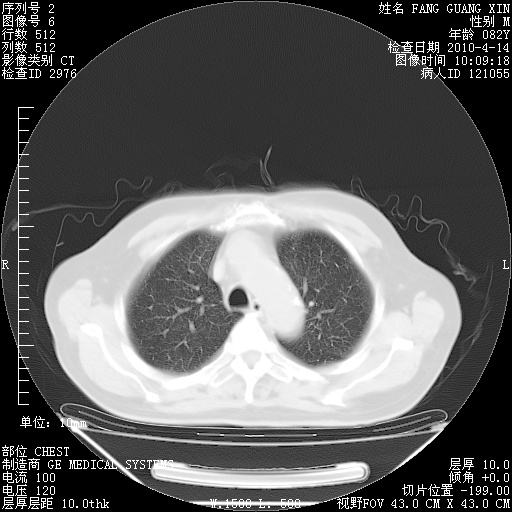

4月14日肺部CT

4月28日肺部CT——再次出现类似去年5月9日——透光度降低,(影像科认为)“间质性”改变。

4月28日肺部CT——再次出现类似去年5月9日——透光度降低,“间质性”改变。